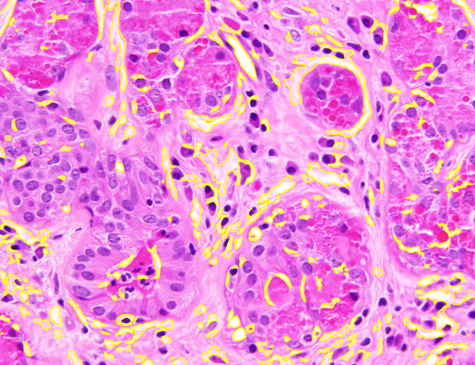

Dataset 1 comprises a synthetic video and two hematoxylin and eosin (H&E)-stained images collected from public online sources [71, 72]. H&E staining is standard in histopathology, with nuclei appearing blue–purple and cytoplasm pink. The images are provided in RGB format with varying image sizes and are used solely for qualitative illustration and timing comparisons, as no ground-truth annotations are available. The synthetic video consists of 74 MATLAB-generated frames. The first frame shows a 3D mitochondrial mesh generated via the isosurface function and rendered with Phong illumination, with the light source positioned above and to the right of the camera. Subsequent frames are obtained by rotating this initial view. This dataset was constructed to study segmentation under pronounced frame-to-frame illumination changes.

Representative samples from the three datasets are shown in Fig. 1. In (a), the first frame of the synthetic video in Dataset 1 illustrates the strong illumination gradients produced by distance-dependent shading together with orientation-dependent interactions between vertex normals and the light direction. The H&E images in (b) and (c), also from Dataset 1, depict a mast cell infiltrate from a patient with non-alcoholic steatohepatitis and cirrhosis and, respectively, a sample from a patient with sclerosing polycystic adenosis of the parotid gland; the former consists primarily of purple nuclei, white cytoplasm, and pink extracellular tissue. Subfigures (d) and (e) show two examples from Dataset 2 accompanied by their ground-truth nuclei annotations, while (f) and (g) present a representative image from Dataset 3 together with its corresponding cell mask.

Figure 1: Samples from Datasets 1–3. (a) First frame of the 74-frame video in Dataset 1 (1770 × 880) with a superimposed red mesh. (b,c) H&E-stained tissue images from Dataset 1 (1000 × 750; 950 × 730). (d,e) Cell images from Dataset 2 (600 × 600) with nuclei annotations. (f,g) Image from Dataset 3 (512 × 512) with annotation.

Figure 10 shows the results for the second hematoxylin–eosin stained image from Dataset 1 (see Fig. LABEL:fig_sub:he2_image). The AR model detected only structures near the initialization, missing many objects. The ZZ model recovered most cells but also introduced numerous unnecessary pink regions, and its two outputs were nearly identical despite different initial level sets (Figs. LABEL:fig_sub:he2_in1_AR-LABEL:fig_sub:he2_in2_AR), similar to the over-segmentation behavior of SAM (Fig. LABEL:fig_sub:he2_out_SAM). SAM, which does not require initialization, failed to separate different structures, while SMST produced too few foreground objects and added spurious regions, without a clear background. In contrast, SP, initialized with 6000 Power-SLIC superpixels (Fig. LABEL:fig_sub:he2_in_SP), achieved accurate separation of nuclei and cytoplasm.

Figure 10: Unsupervised segmentation of the image in Fig. LABEL:fig_sub:he2_image for two structures: purple cells (S1) and white cytoplasm (S2). Initializations via level sets (LS) for AR and ZZ are shown in (a, b); 6000 superpixels for SMST and SP in (c) (red channel for S1, remaining channels for S2). SAM does not allow separate-channel segmentation; its overall output is in (d). Results for S1 are in (e–h) and for S2 in (i–l). Computation times (S1/S2, in seconds): AR 461.85/474.46, ZZ 2423.73/2434.59, SMST 0.42/0.38, SP 42.31/12.51; superpixels in (c) computed in 0.14s, SAM in (d) in 7.47s.